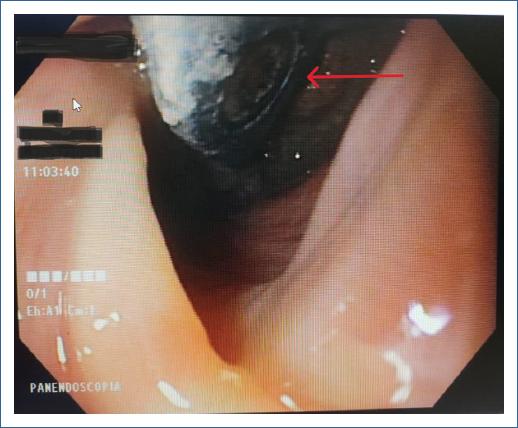

Mujer de 64 años de edad con antecedente de abordaje anterior cervical con colocación de material protésico a nivel de C5-C7 hace seis años por patología degenerativa de la columna cervical, donde se produce una perforación esofágica, la cual es manejada con cierre primario + gastrostomía en el mismo acto quirúrgico; a los pocos días del posquirúrgico presenta fistula esófago-cutánea con gasto siálico, el cual se maneja de forma conservadora (Figs. 1 y 2). Ante el cese de gasto de fistula se inicia tolerancia de alimentos con adecuada respuesta; a los dos años presenta leve disfagia a sólidos, para lo cual se realiza panendoscopia de control, la cual reporta estenosis 20% franqueable a nivel de cricofaríngeo. La paciente continúa con valoraciones frecuentes de manera anual por parte del servicio de endoscopia, sin embargo, ante la presencia de mayor disfagia a sólidos y en el último mes a líquidos, se realiza valoración endoscópica a los seis meses de su último control donde se identifica estenosis esofágica 50% + material de osteosíntesis en la luz esofágica a nivel del cricofaríngeo, hallazgo no encontrado en su último control (Fig. 3). Paciente al momento de su valoración hemodinámicamente estable, sin respuesta inflamatoria, sin sepsis, sin dolor; sin embargo, con alto riesgo de osteomielitis a nivel cervical, por lo cual se envía al servicio de cirugía de columna para valoración de los hallazgos descritos.

Figura 3 Material de osteosíntesis en la luz esofágica posterior a nivel del cricofaríngeo.